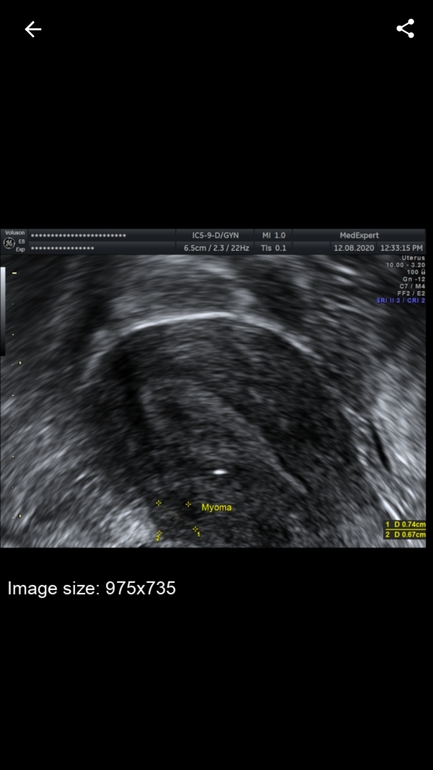

Действительно ли это миома или что это?

У меня задержка, сходила на узи, узистке точно не понятно что это, ставит миому под ?

Ну размер то достаточный для определения. Узисты обычно видят миому и не путают. Дело не в оборудовании, тут оно хорошее. Если врачу не доверяете,я бы переделала. Некоторым практики не хватает для точного определения и тогда начинают гадать: миома, полип и прочее.